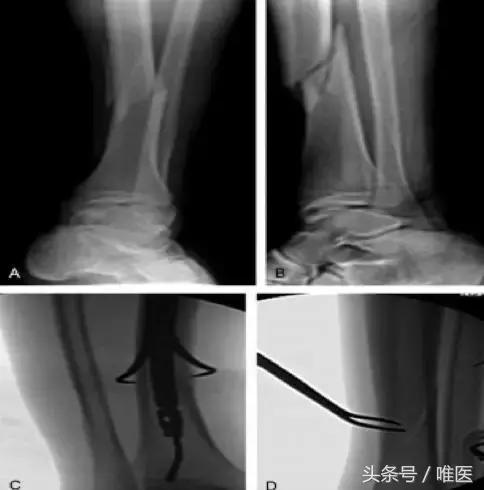

◎ 经皮使用尖嘴复位钳复位 闭合骨折使用尖嘴复位钳的点对点钳夹复位效果良好,特别是螺旋及斜行骨折。微创经皮放置尖嘴钳,提供骨折块间的加压。保持复位,直到髓内钉置入指定位置(图1)。

图1 经皮Weber钳复位 斜行骨折(A和B)相对简单的胫骨远端骨折经皮放置尖嘴钳复位,对软组织影响小微创。(C和D)